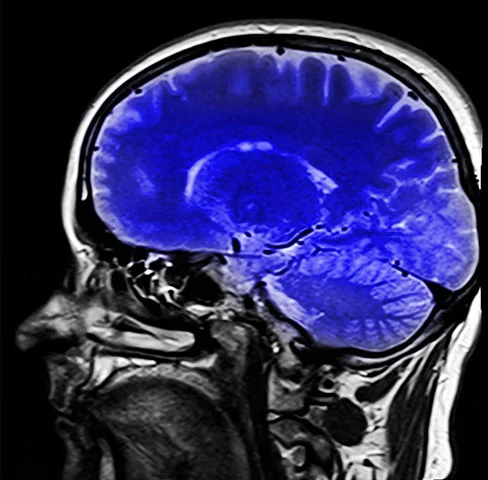

Nutriente vital para o bom desenvolvimento do cérebro é pouco conhecido; veja alimentos com ‘colina’